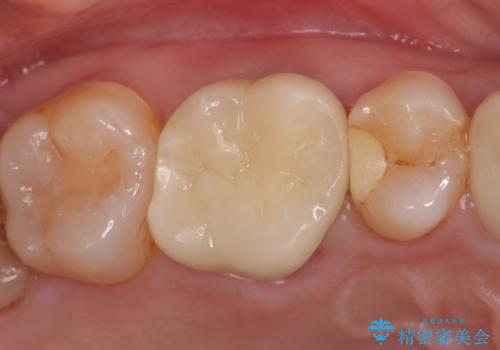

オールセラミッククラウン メタルフリーのクラウンへ

セラミックインレー 冷たいものがしみる奥歯の治療